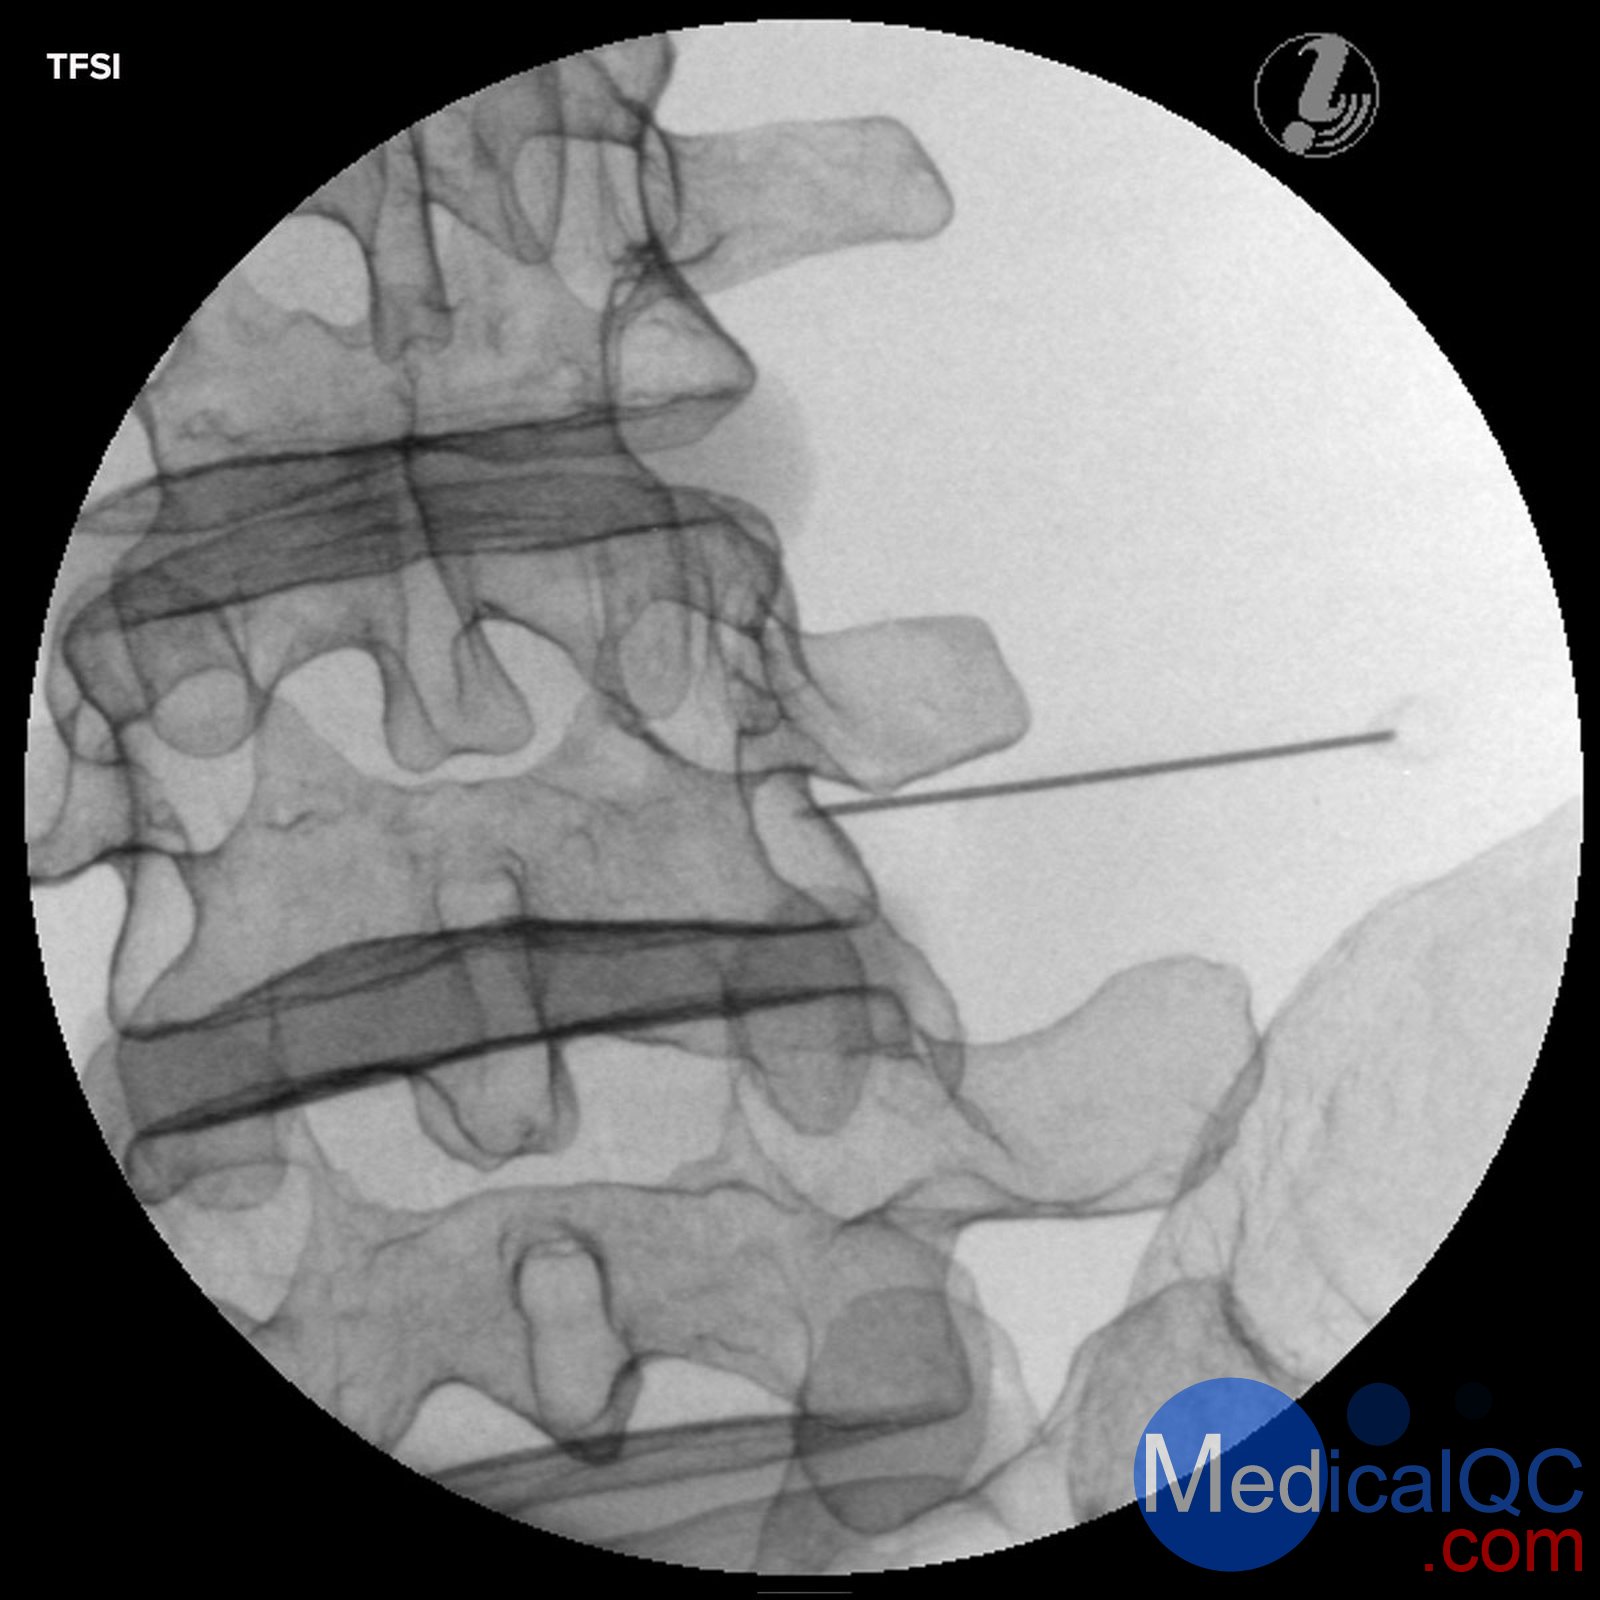

經顱內硬膜外類固醇注射(TFSI)

Image Guided Lumbar Spinal Injection Trainer

Improve outcomes of spine interventions with standardized image guided injection training

The Image Guided Lumbar Spinal Injection Trainer enables trainees to develop a three-dimensional understanding of the procedures for successful spine interventions. They will learn to correlate imaging with the lumbar spinal anatomy relevant to interventional pain procedures, to identify the target tissue and vulnerable structures using imaging and anatomic inspection, and to apply best practices to ensure patient safety during the interventional spine procedures.

Using the Spinal Injection Trainer is an economic alternative for imaging techniques courses on cadavers and offers the instructors a reliable, standardized patient simulation always ready to use:

Life-like radiopacity for realistic x-Ray images

Realistic injection haptics

Anatomically accurate bone structure

Visually identifiable landmarks

The following image guided spinal interventions can be trained on the simulator:

Transforaminal Epidural Steroid Injections (TFSI)